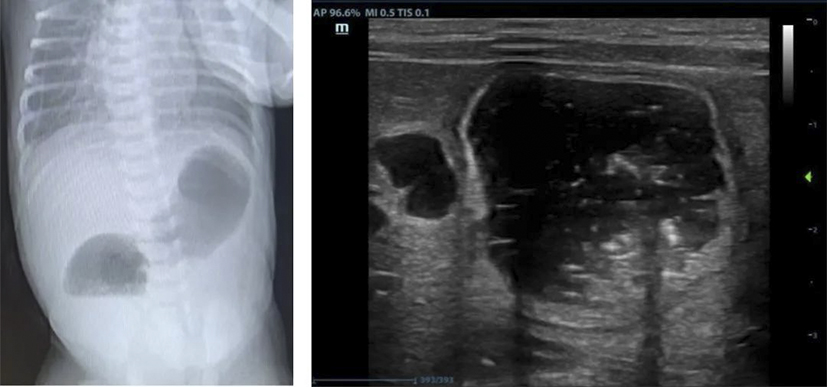

十二指腸閉鎖是一種先天性消化道畸形,發(fā)病率約1/50000至1/10000,占所有腸閉鎖的50%以上,約30%合并唐氏綜合征,也可能伴隨其他先天異常(如心臟畸形、腸旋轉(zhuǎn)不良等)。產(chǎn)前主要表現(xiàn)為母體羊水過多,超聲可見胃和十二指腸近端擴(kuò)張(“雙泡征”)。出生后表現(xiàn)為24-48小時內(nèi)嘔吐、上腹部膨隆、排便減少或無胎糞排出等。通過產(chǎn)前超聲、出生后X線檢查可以明確診斷,手術(shù)是唯一的治療方法。微創(chuàng)腹腔鏡手術(shù)具有創(chuàng)傷小、出血少、術(shù)后恢復(fù)快、縮短住院時間等優(yōu)勢,目前已廣泛應(yīng)用于十二指腸閉鎖的治療。

該患兒母親孕期產(chǎn)檢中四維彩超提示胎兒十二指腸狹窄或閉鎖可能,一直在我院產(chǎn)科、超聲科、小兒外科的MDT團(tuán)隊(duì)門診隨訪監(jiān)測,直至足月后剖宮產(chǎn)娩出。嬰兒轉(zhuǎn)至新生兒科進(jìn)一步完善超聲、消化道造影明確診斷為十二指腸閉鎖,急需手術(shù)治療。